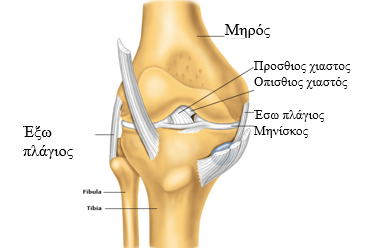

Ο πρόσθιος χιαστός σύνδεσμος είναι ένα βασικό ανατομικό στοιχείο που σταθεροποιεί την άρθρωση του γόνατος.

Μαζί με τον οπίσθιο χιαστό σύνδεσμο, βρίσκονται σε κεντρική θέση μέσα στην άρθρωση, και σε συνδυασμό με τους πλάγιους συνδέσμους (έσω και έξω πλάγιο) σταθεροποιούν και επιτρέπουν την ομαλή κίνηση του γονάτου.